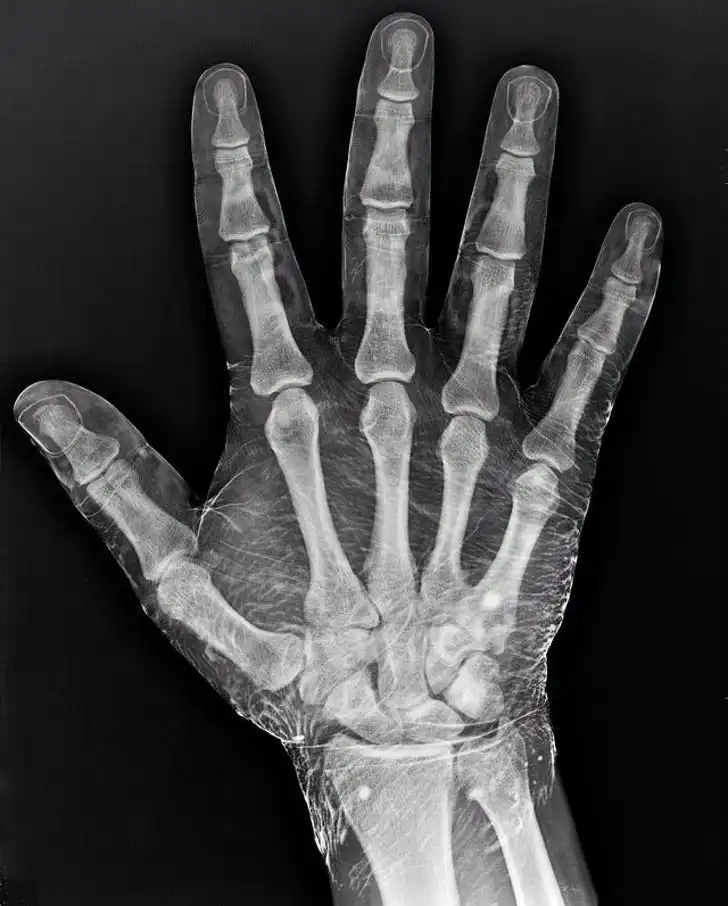

Рентгенография руки, смоченной в йоде. Йод поглощает рентгеновские лучи и подсвечивает кожу вокруг костей, отчего она кажется прозрачной